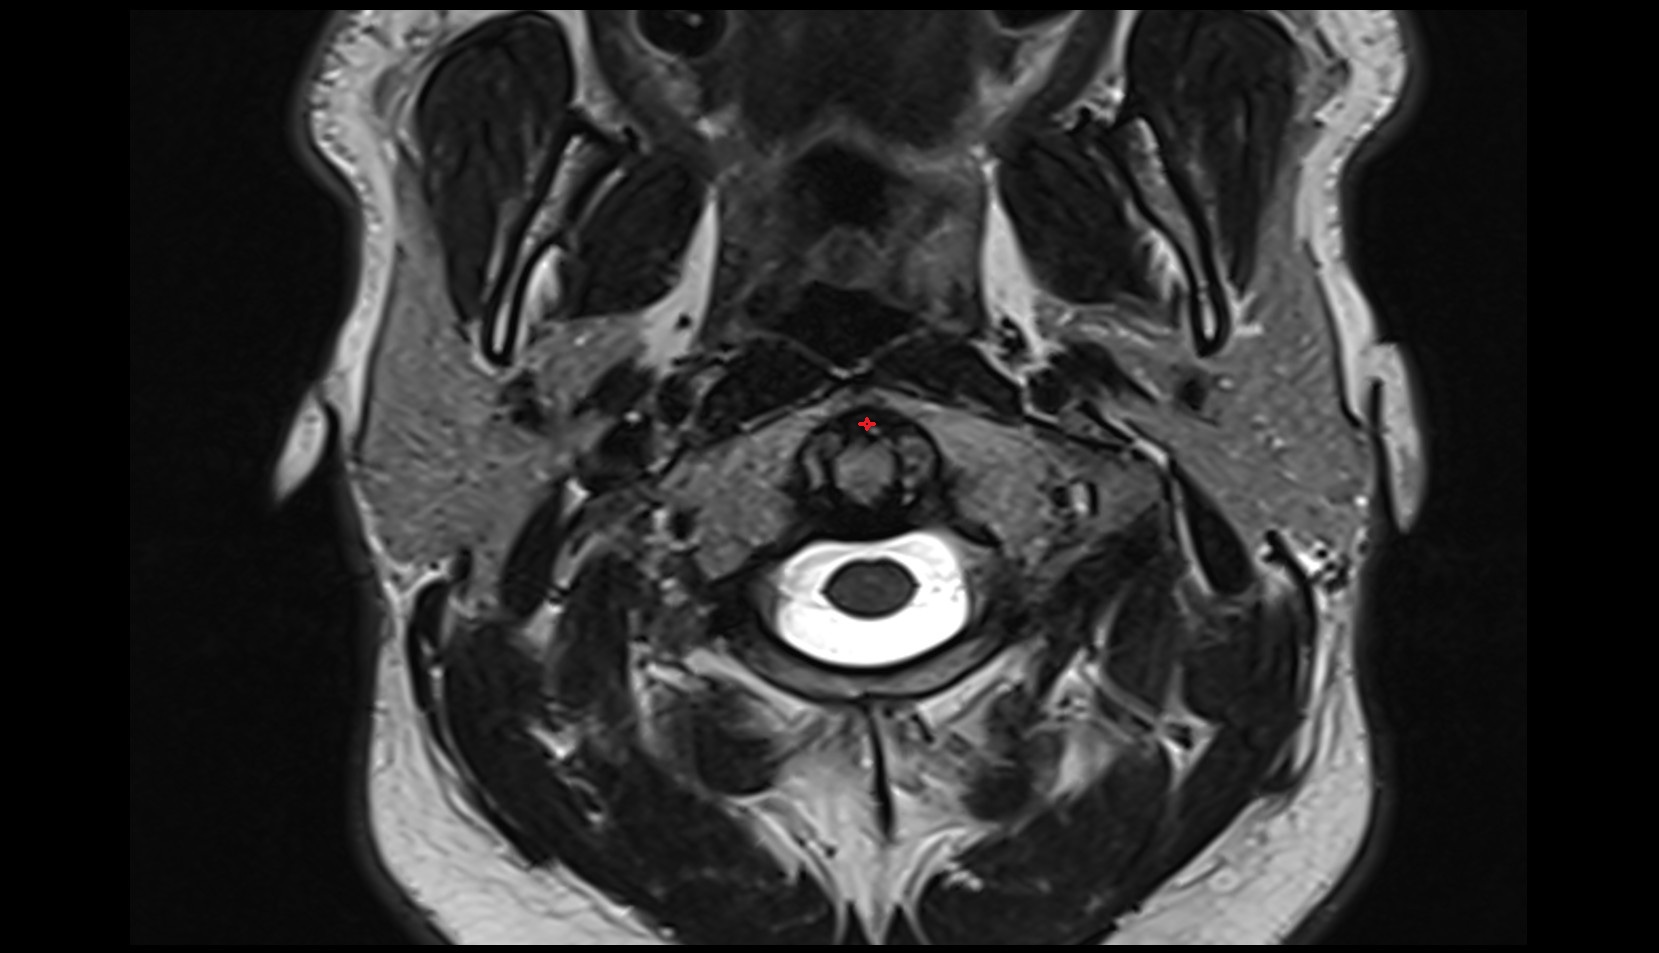

- Peripheral zone of prostate

- Anterior Fibromuscular Stroma of prostate

- Central zone of prostate

- Transitional zone of prostate